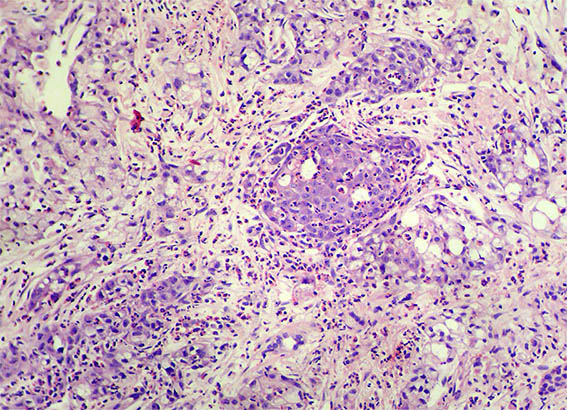

Figura 2. H&E, X100.